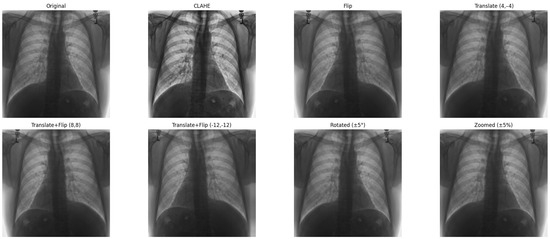

Figure 7 shows examples of images to which data augmentation techniques have been applied. Table 4 provides a detailed explanation of the types of data augmentation, their settings, and their clinical purposes.

Figure 7.

Data augmentation example.

Horizontal flipping was applied with a 50% probability, as frontal chest radiographs maintain diagnostic validity regardless of left–right symmetry in most cardiomegaly cases [29].

Rotation was constrained to a small range of ±5 degrees, as larger rotations could deform key structures such as the heart silhouette or mediastinum, which are essential for accurate diagnosis.

Zoom augmentation was applied within a narrow range of 95% to 105%, simulating realistic changes in radiographic magnification during image acquisition while avoiding the disproportionate enlargement of the heart or lungs.

Translation was limited to ≤5% of the image width or height (i.e., maximum shifts of approximately ±10 to 12 pixels) along the x- and y-axes to simulate minor variations in patient positioning without displacing core anatomical features.

Additionally, combinations of flipping and translation were used selectively to further enhance spatial diversity without compromising clinical interpretability [29].